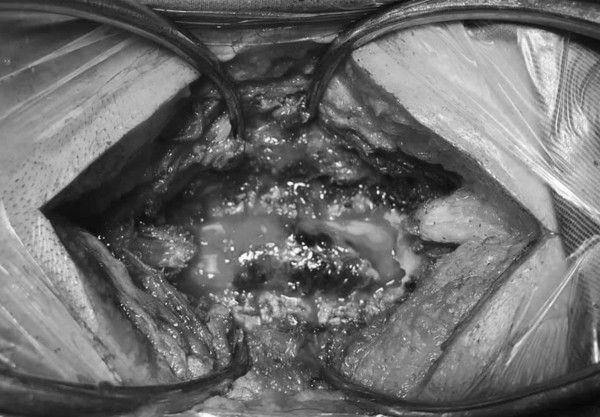

Ca mổ cấp cứu được tiến hành lúc gần nửa đêm và kết thúc sau đó 2 tiếng, khối máu tụ lớn trong cột sống cổ của bệnh nhân được lấy bỏ, giải phòng chèn ép tuỷ thần kinh. Sau mổ bệnh nhân thở yếu nên nằm hồi sức 3 ngày rồi chuyển về khoa phòng. Ngày thứ 5 sau mổ, “điều kỳ diệu đã xảy ra”, chân bệnh nhân vận động trở lại được như bình thường.

![]() |

| Khối máu tụ (màu đen) chèn ép tủy đố sống cổ |